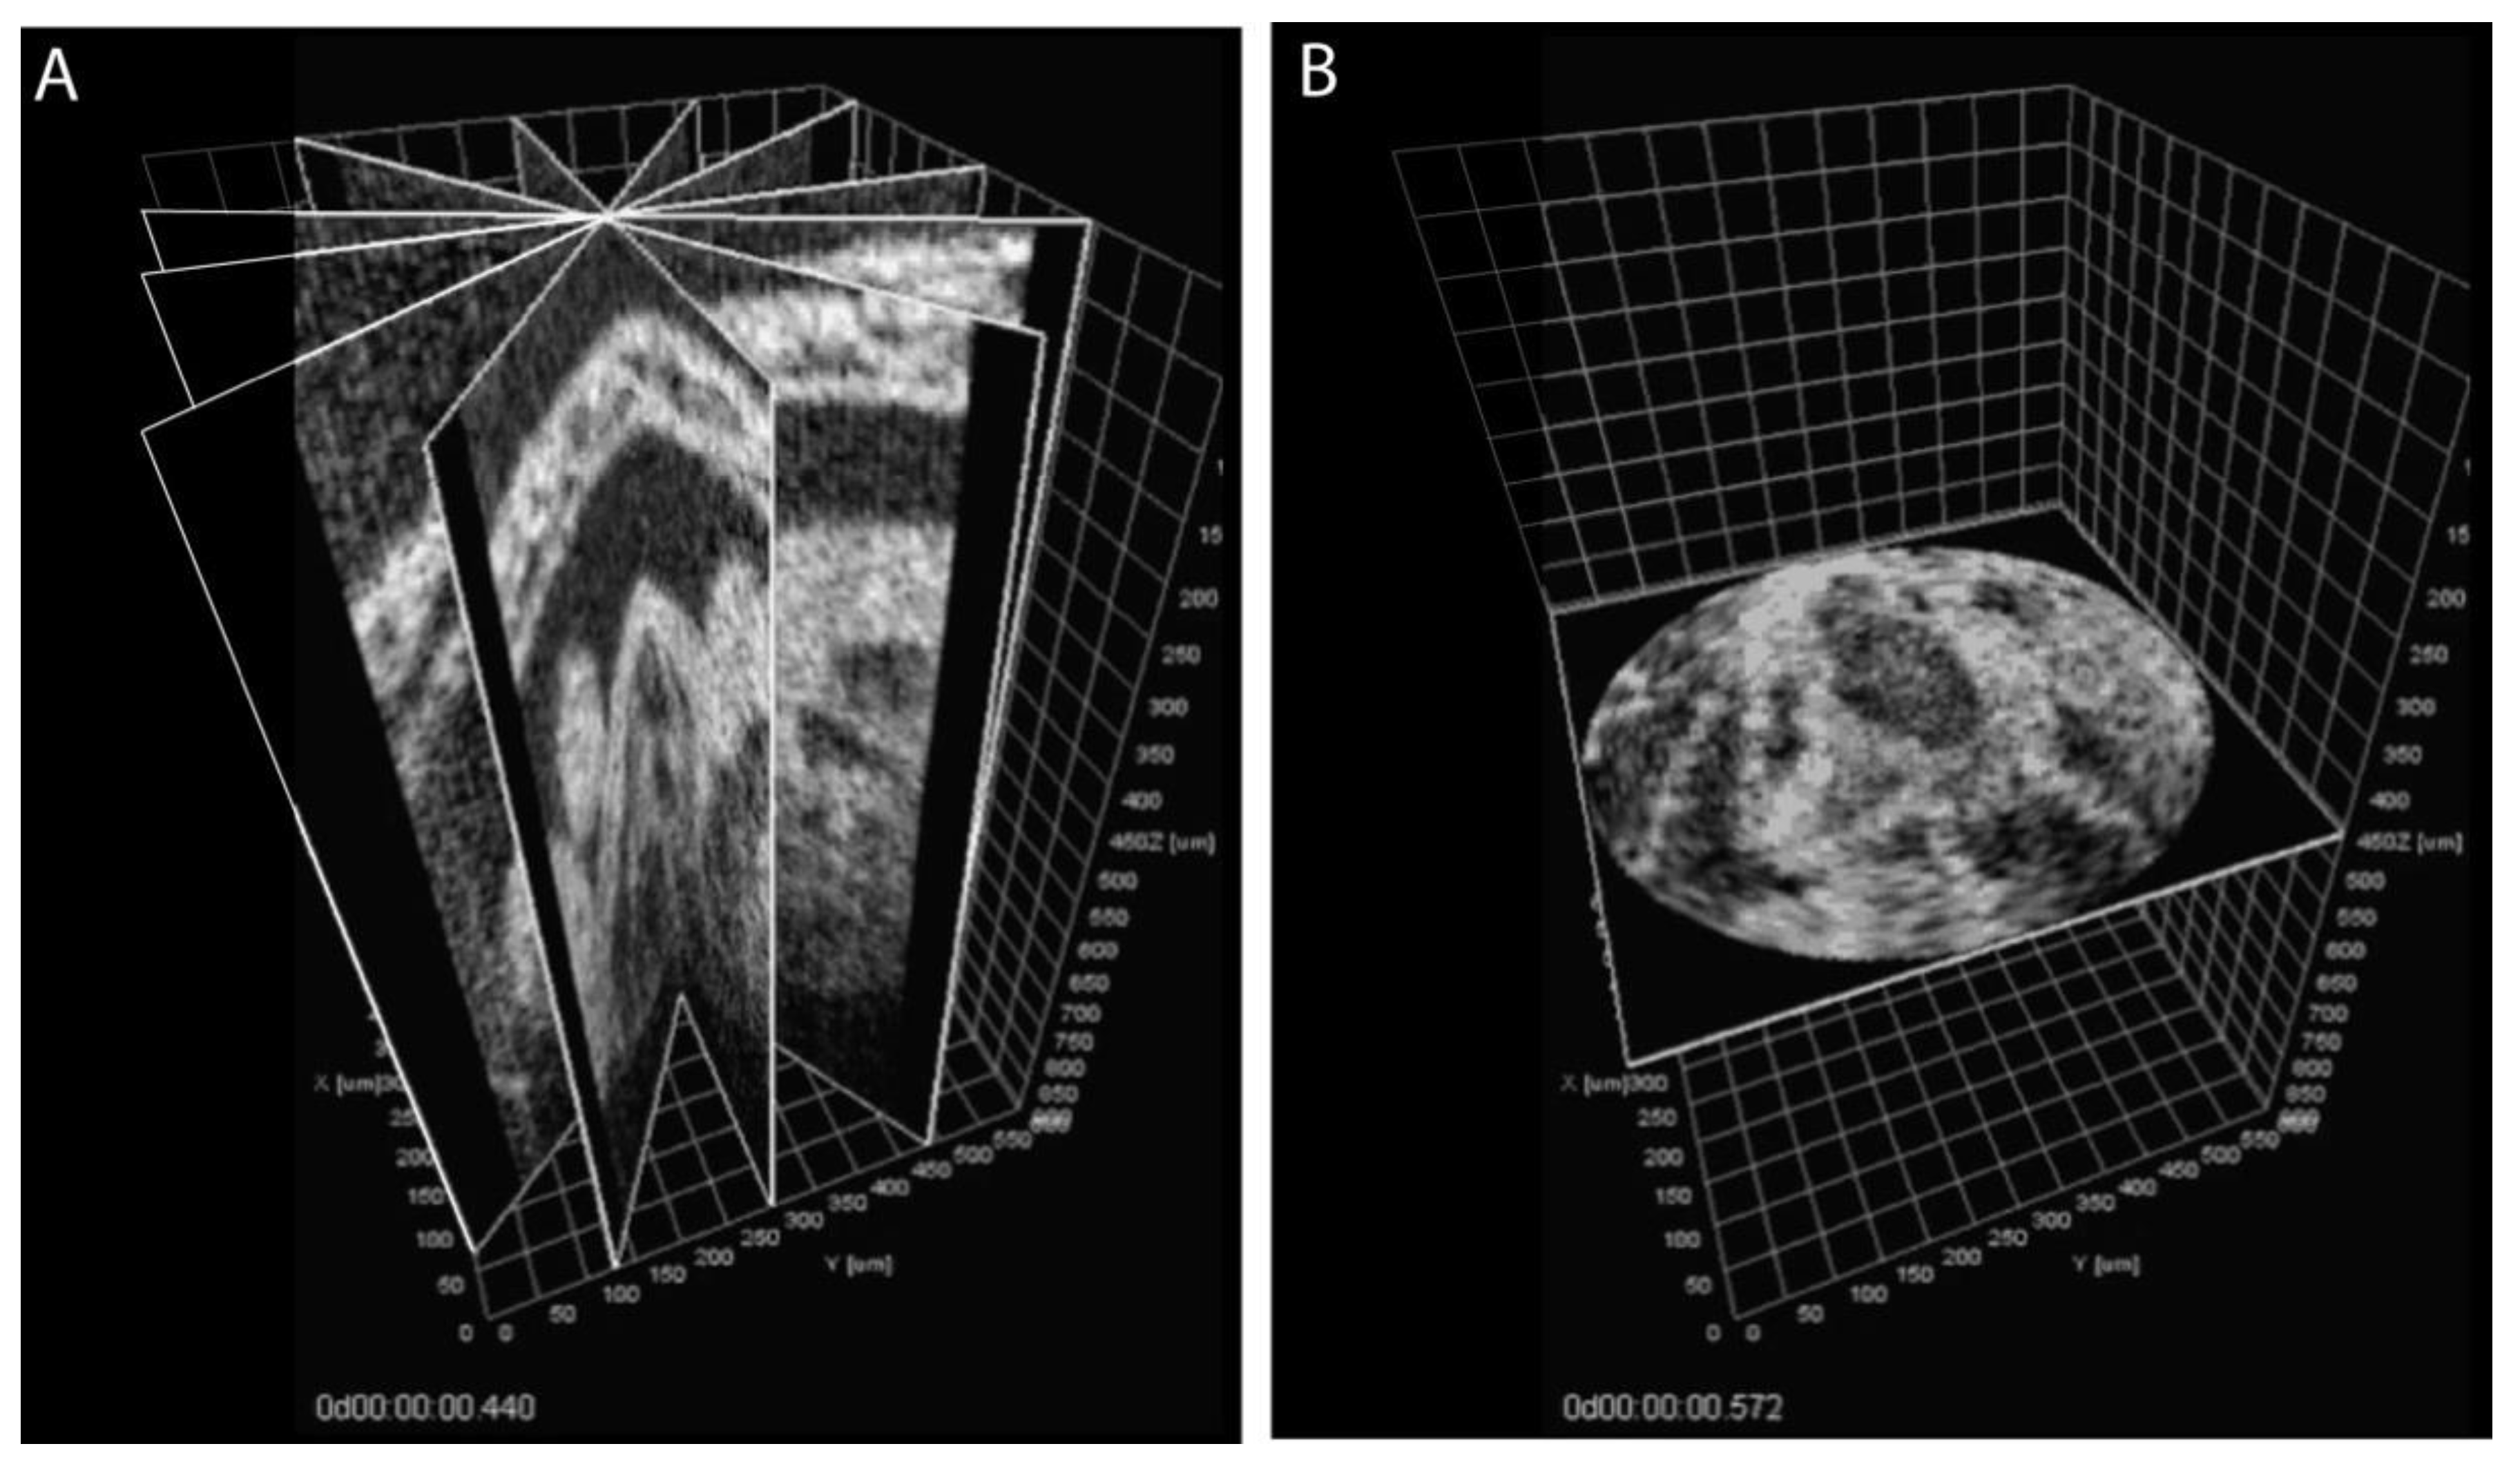

3. Approaches to Volumetric Cardiodynamic Imaging

- Larina, I.V.; Larin, K.V.; Dickinson, M.E.; Liebling, M. Sequential Turning Acquisition and Reconstruction (STAR) method for four-dimensional imaging of cyclically moving structures. Biomed. Opt. Express 2012, 3, 650–660. [Google Scholar] [CrossRef] [Green Version]

- Bhat, S.; Larina, I.V.; Larin, K.V.; Dickinson, M.E.; Liebling, M. 4D reconstruction of the beating embryonic heart from two orthogonal sets of parallel optical coherence tomography slice-sequences. IEEE Trans. Med. Imaging 2013, 32, 578–588. [Google Scholar] [CrossRef] [Green Version]